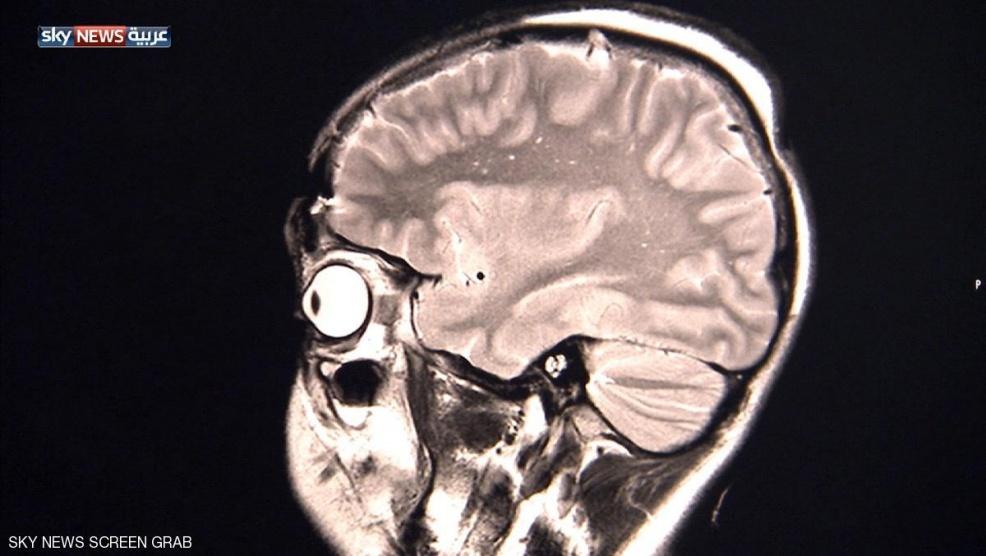

شبكة وتر-أجرى العلماء لأول مرة فحوصا بالأشعة المقطعية على أدمغة أشخاص تعاطوا العقار المخدر (إل إس دي)، وقالوا إنه يزيل الفواصل بين مناطق الدماغ المختلفة ليتصرف الشخص كما لو كان طفلا.

قال فريق بحثي تحت إشراف "إمبريال كوليدج" في لندن إن المخ يعمل عادة وفقا لشبكة عصبية ذات مناطق منفصلة تؤدي كل منها وظيفة مختلفة كالرؤية والحركة والسمع وغيرها، لكن عند تعاطي هذه العقاقير المخدرة تزول هذه الفواصل وتنهار الشبكة العصبية ليتصرف المخ كوحدة واحدة.

وأظهرت النتائج -التي وردت الاثنين في دورية الأكاديمية القومية للعلوم- أنه عندما تعاطى المتطوعون العقار المخدر شارك الكثير من مناطق المخ الإضافية في عملية الرؤية والإبصار مثلا وليس مجرد القشرة المسؤولة عن ذلك بمفردها.

وتضمنت الدراسة 20 متطوعا سليما في مركز للبحوث لا يعانون من مشاكل جسمية أو نفسية وكانوا قد تعاطوا مثل هذه العقاقير من قبل، مع الاستعانة بفحوص منها التصوير الوظيفي بالرنين المغناطيسي والتصوير المغناطيسي للدماغ لدراسة نشاط المخ والأنشطة الكهربية وتدفق الدم.